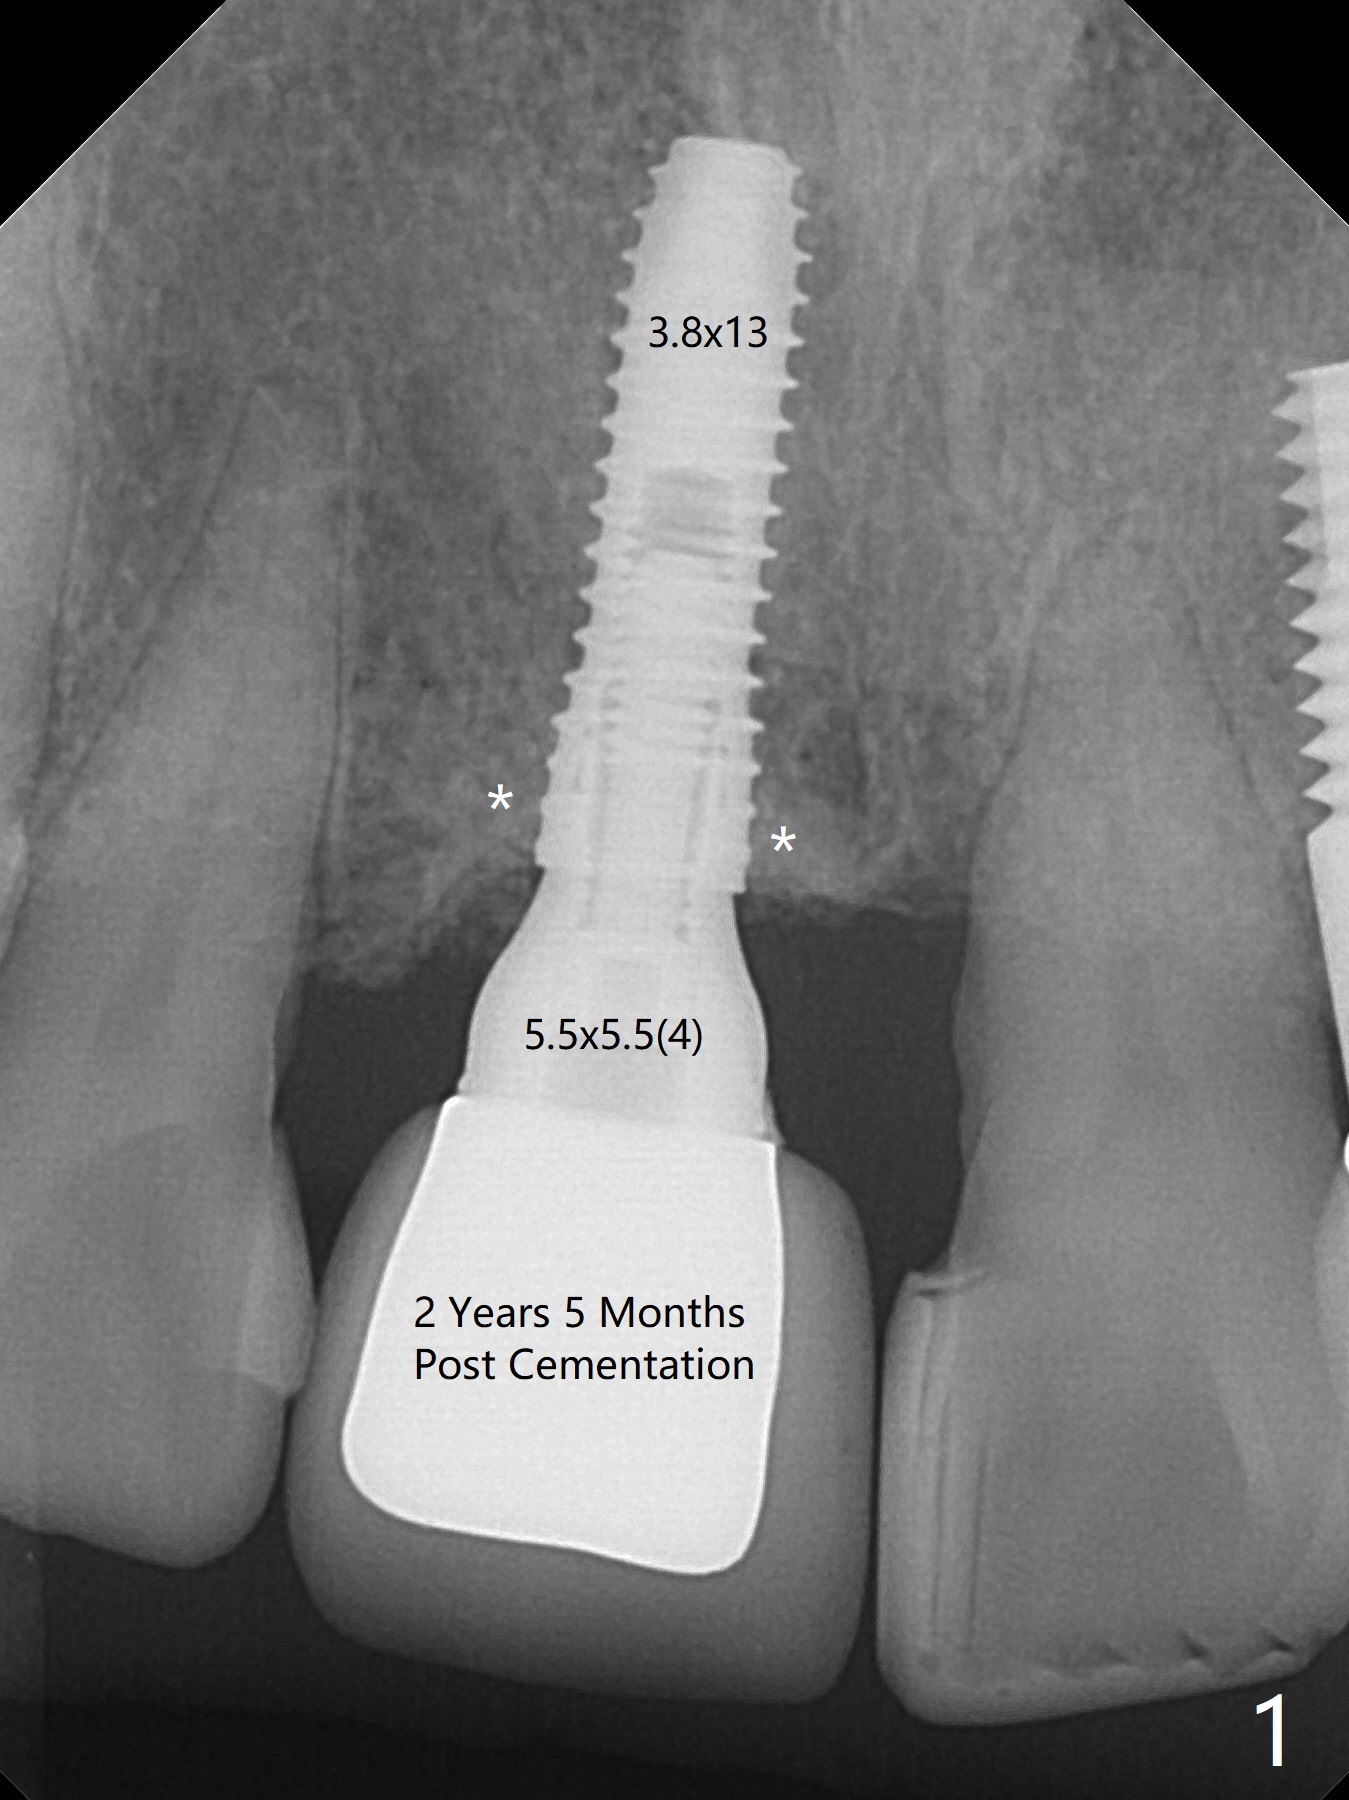

A 52-year-old woman returns for follow up 2-3 years post cementation (Fig.1-3). A smaller implant in the anterior maxilla appears to be associated with bone growth (Fig.1 * (#8)), as compared to a larger one (Fig.2 (#10)). There is apparently no bone loss at #31 (Fig.3).